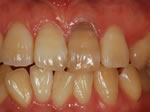

術前

→

術後